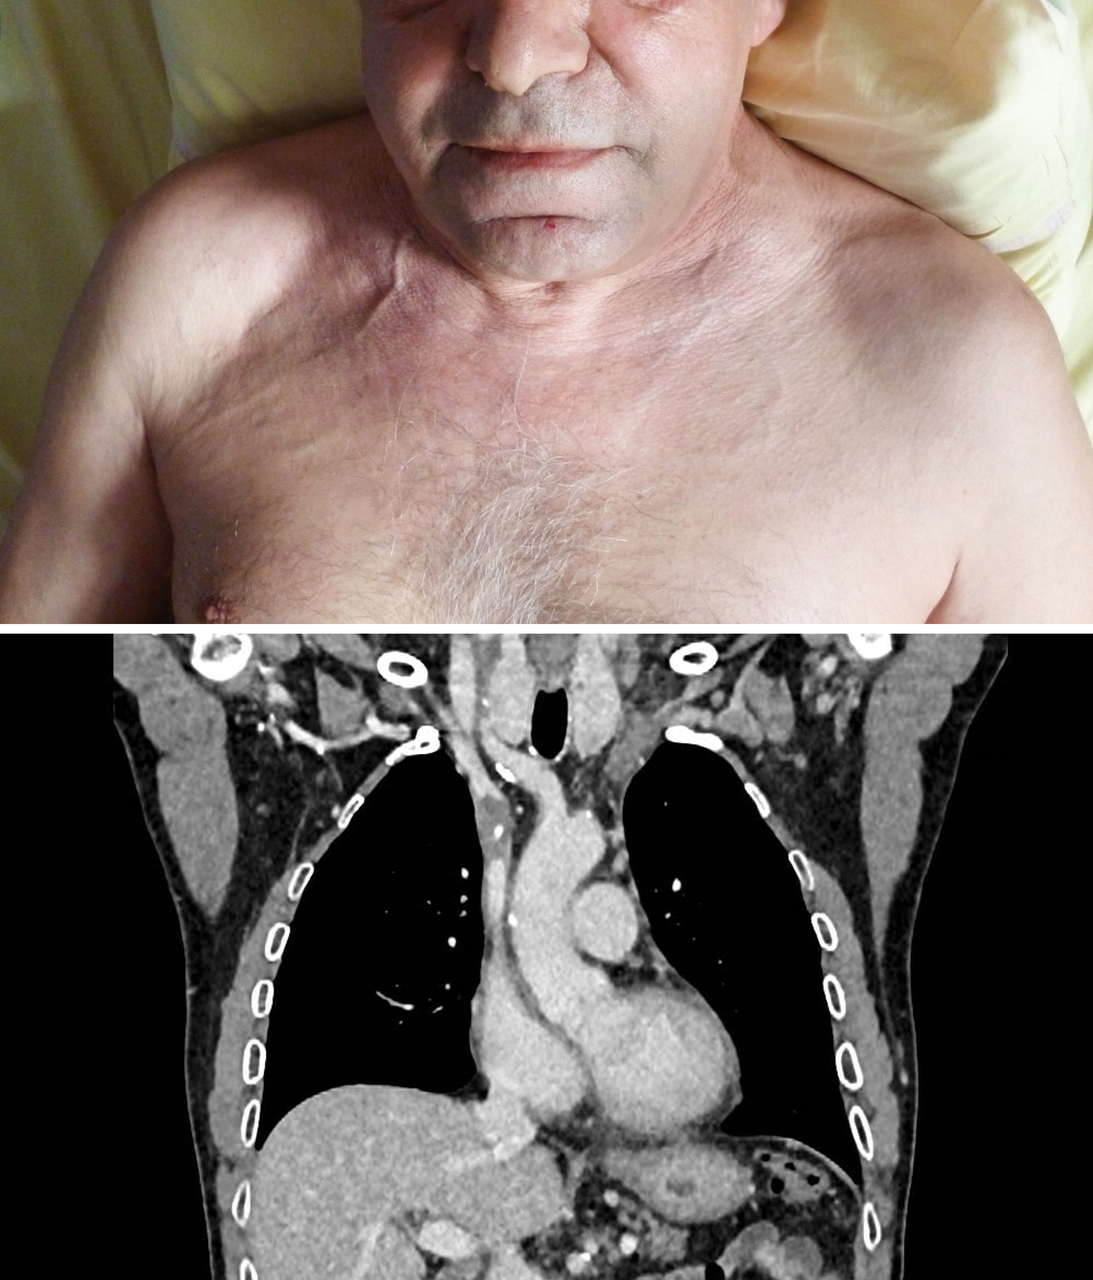

Un homme de 60 ans est suivi pour un adénocarcinome gastrique depuis trois ans. Il est hospitalisé pour un œdème de la face et de la région cervicale, avec comblement des creux sus-claviculaires et une turgescence jugulaire. Un angioscanner est réalisé.

L’angioscanner montre une thrombose d’allure récente du tronc veineux innominé, étendue à la veine cave supérieure.

Deux ans auparavant, le patient avait eu un premier épisode de thrombose cave supérieure sur chambre implantable.

Le syndrome cave supérieur est le plus souvent la conséquence de la compression de la veine cave supérieure par un processus tumoral (cancer bronchique, lymphome...). Il peut être secondaire à une thrombose in situ favorisée notamment par la présence d’un dispositif intravasculaire (chambre implantable).